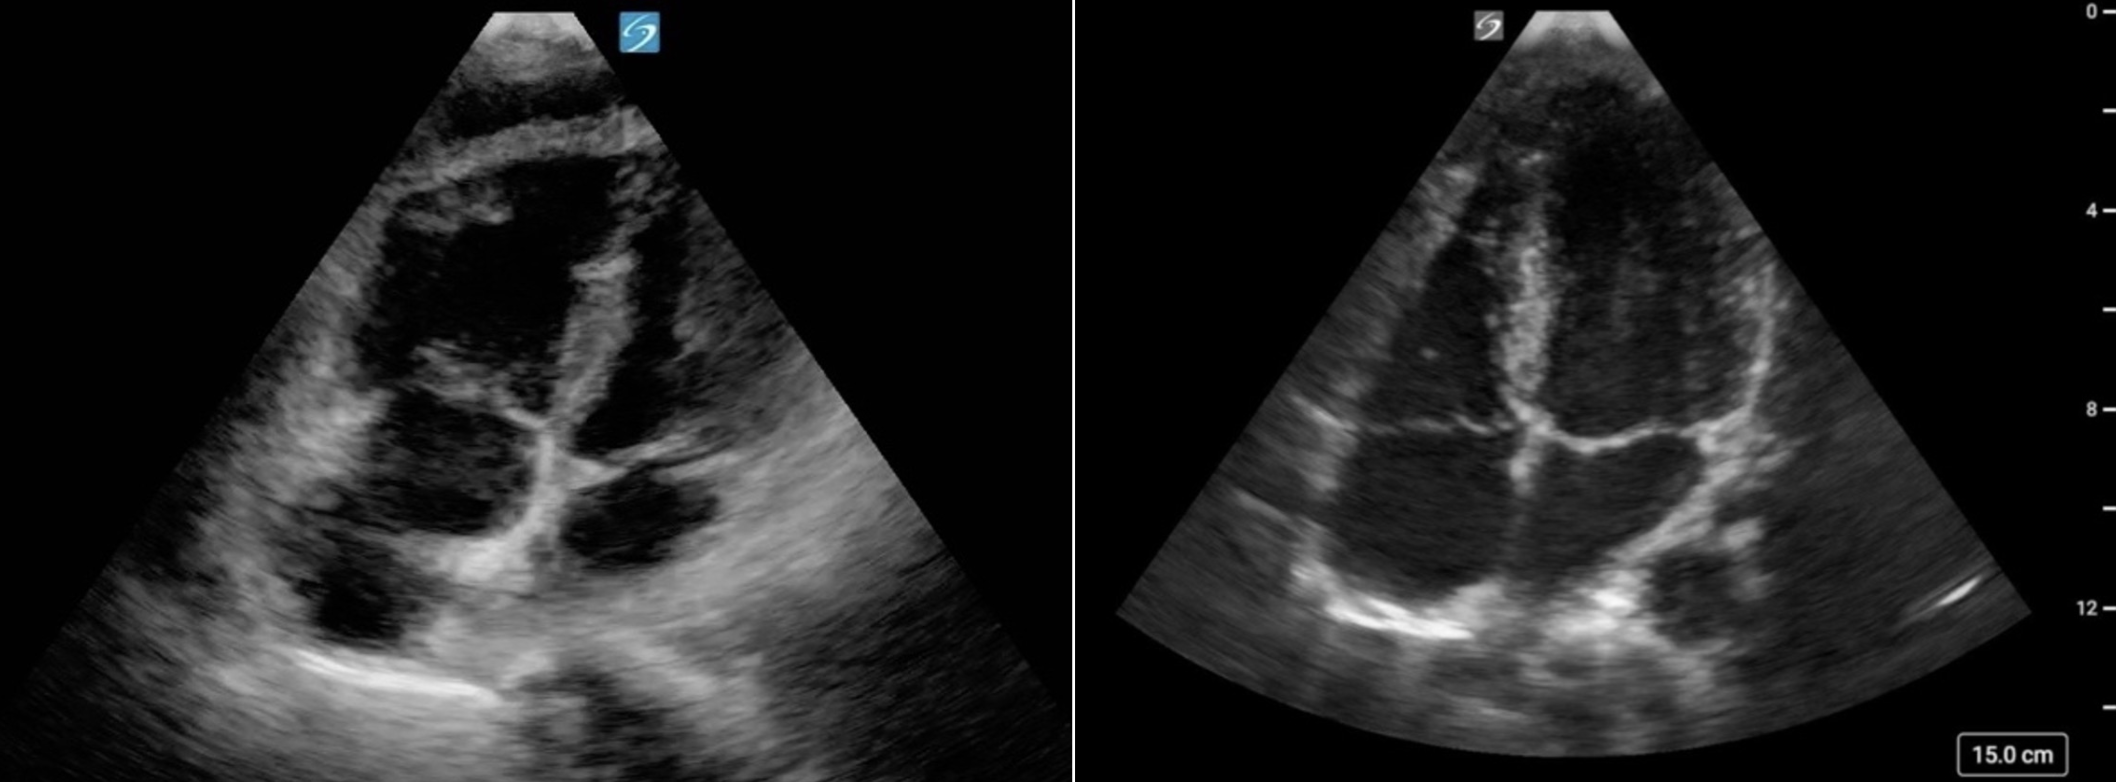

Similar to LV function assessment, RV strain imaging is susceptible to foreshortening and off-axis imaging. In the PSAX window, a low imaging window or off-axis rotation can produce apparent septal flattening (“pseudoflattening”) (figure 24, 25), which may mimic RVVO and/or RVPO and lead to inappropriate conclusions or interventions [17, 24,25]. In the A4C view, foreshortening may occur when imaging from too high of an intercostal space, making the RV appear truncated or blunted (figure 26,27). Always confirm you are at the appropriate intercostal space by scanning through adjacent levels in each window.

Figure 26. Foreshortened RV in the A4C view

Figure 27. (a) Foreshortened RV in the A4C view. Note the blunted RV apex and loss of the triangular apical tip compared to (b) Elongated RV with triangular tip in the A4C view

Figure 28: A4C cardiology convention, showing RV dilation alongside LV dilation. Although the RV appears smaller than the LV, it is also enlarged.